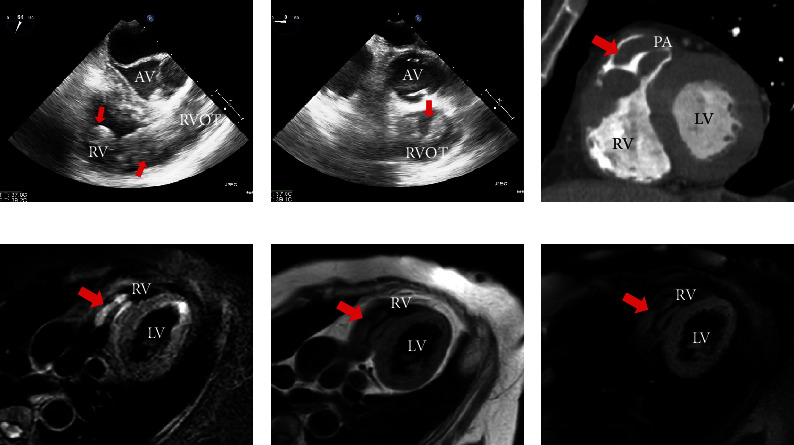

未分化子宫肉瘤(undifferentiated子宫sarcoma, UUS)是一种罕见且具侵袭性的子宫肿瘤。因此,我们对UUS作为心脏转移的主要部位知之甚少。我们报告一例66岁女性,子宫肌瘤病史30年,因子宫大肿瘤及心脏肿块住院治疗。尽管我们使用超声、心脏计算机断层扫描和磁共振成像等成像方式研究了心脏肿块,但很难确定肿块是转移灶还是血栓。心脏肿块通过手术切除以评估组织特征,后来因其外观被确定为肿瘤。病理结果显示UUS向右心室扩散。我们在手术后尝试化疗;然而,病情进展很快,患者于入院第49天死亡。在这篇报告中,我们描述了一个诊断困难且疾病进展迅速的UUS心脏转移的病例。

Although cardiac metastasis of malignant tumors has often been reported, undifferentiated uterine sarcoma (UUS) is a rare and aggressive uterine tumor. Thus, little is known of the UUS as a primary site of cardiac metastasis. We report a case of a 66-year-old woman, with a history of uterine myoma for 30 years, who was hospitalized with a large uterine tumor and cardiac masses. Although we investigated cardiac masses using imaging modalities, such as ultrasound, cardiac computer tomography, and magnetic resonance imaging, it was challenging to determine the masses as metastasis or thrombi. Cardiac masses were removed by surgery to assess the tissue characteristics and were later identified as tumors due to their appearance. Then, pathological findings revealed that UUS spreads to the right ventricle. We attempted chemotherapy after surgery; however, the disease progressed very quickly and the patient died on the 49th day of admission. In this report, we described the case of a patient with a difficult diagnosis and rapid disease progression of cardiac metastasis from UUS.